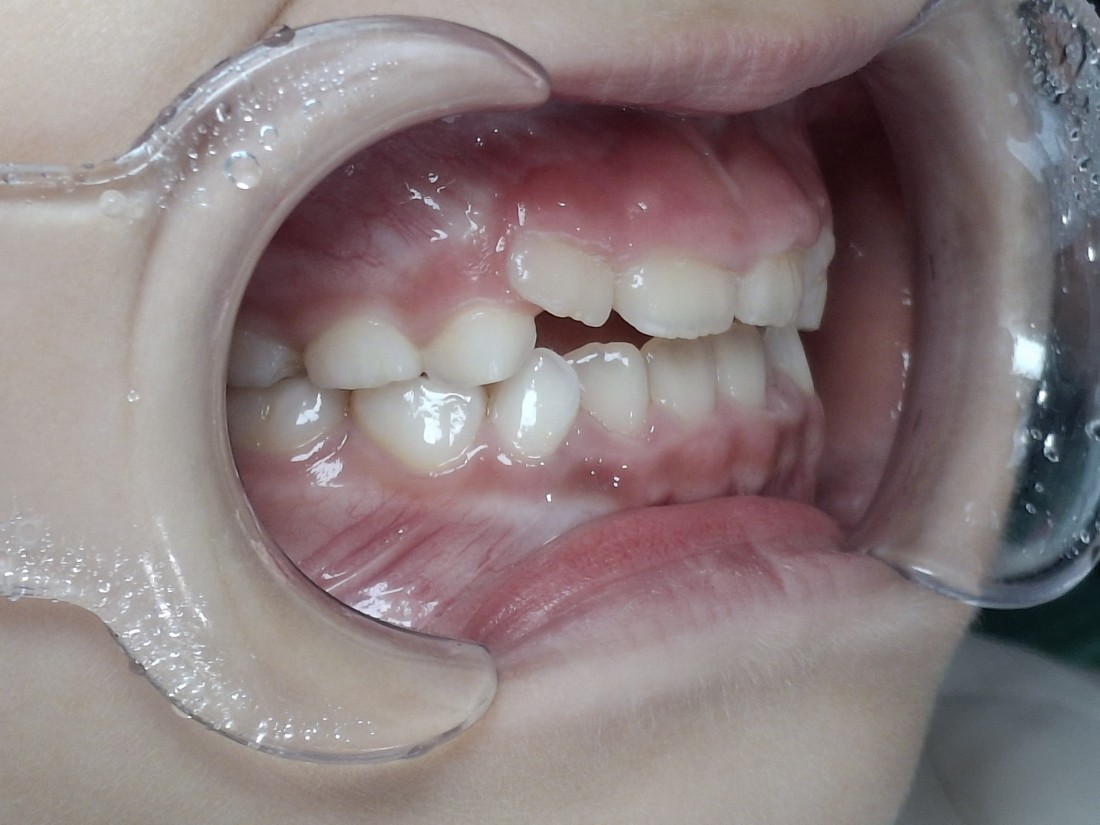

모든 소아 진료실은

1인 룸 진료실로 운영되고 있으며,

소아 진료만을 전담으로 하는

소아 전담 치위생사 선생님과 함께

프리올소 사용방법을 익히고

착용일지를 작성하고 있기 때문에

더욱 치료효과가 좋습니다.